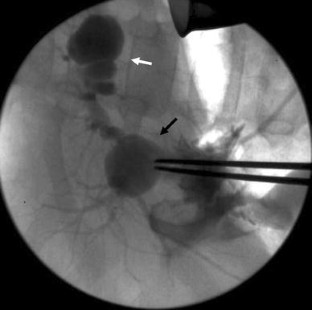

Choledochal cysts are rare, congenital malformations of the intra and/or extrahepatic biliary tree. We describe a case in which a patient was transferred to our hospital with a reported duodenal hematoma. The patient ultimately required exploration when his condition deteriorated. Laparotomy resulted in the discovery and successful treatment of a ruptured type IV-A choledochal cyst.

Fig. 2